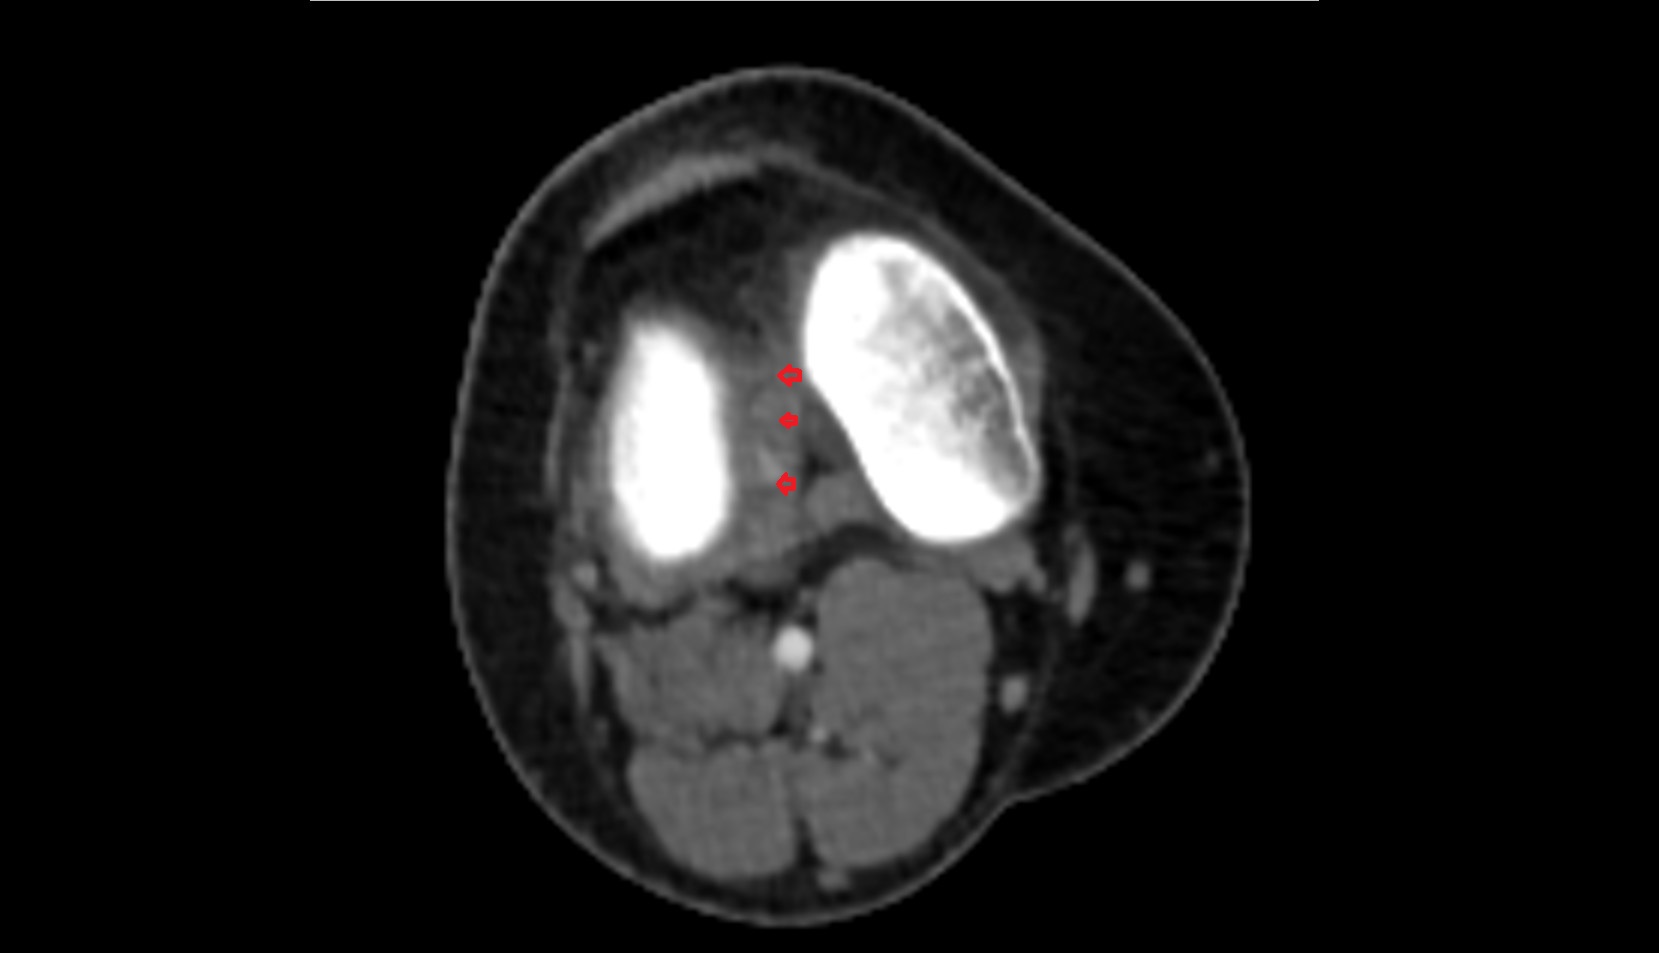

- Popliteal artery

- Popliteal vein

- Lateral condyle of femur

- Medial condyle of femur

- Medial tibial plateau

- Lateral tibial plateau